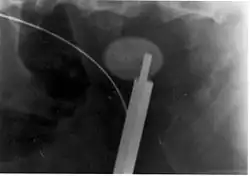

Where a CT scan is unavailable, an intravenous pyelogram may be performed to help confirm the diagnosis of urolithiasis. This involves intravenous injection of a contrast agent followed by a KUB film. Uroliths present in the kidneys, ureters, or bladder may be better defined by the use of this contrast agent. Stones can also be detected by a retrograde pyelogram, where a similar contrast agent is injected directly into the distal ostium of the ureter (where the ureter terminates as it enters the bladder).[61]

Ureteroscopy has become increasingly popular as flexible and rigid fiberoptic ureteroscopes have become smaller. One ureteroscopic technique involves the placement of a ureteral stent (a small tube extending from the bladder, up the ureter and into the kidney) to provide immediate relief of an obstructed kidney. Stent placement can be useful for saving a kidney at risk for postrenal acute kidney failure due to the increased hydrostatic pressure, swelling and infection (pyelonephritis and pyonephrosis) caused by an obstructing stone. Ureteral stents vary in length from 24 to 30 cm (9.4 to 11.8 in) and most have a shape commonly referred to as a "double-J" or "double pigtail", because of the curl at both ends. They are designed to allow urine to flow past an obstruction in the ureter. They may be retained in the ureter for days to weeks as infections resolve and as stones are dissolved or fragmented by ESWL or by some other treatment. The stents dilate the ureters, which can facilitate instrumentation, and they also provide a clear landmark to aid in the visualization of the ureters and any associated stones on radiographic examinations. The presence of indwelling ureteral stents may cause minimal to moderate discomfort, frequency or urgency incontinence, and infection, which in general resolves on removal. Most ureteral stents can be removed cystoscopically during an office visit under topical anesthesia after resolution of urolithiasis.[116] Research is currently uncertain if placing a temporary stent during ureteroscopy leads to different outcomes than not placing a stent in terms of number of hospital visits for post operative problems, short or long term pain, need for narcotic pain medication, risk of UTI, need for a repeat procedure or narrowing of the ureter from scarring.[117]